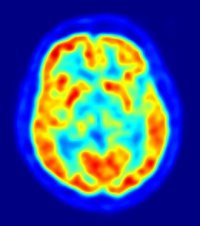

Después, todas estas personas pasaron por imágenes de resonancia magnética, con las que se construyeron mapas muy exactos de su cerebro. Los investigadores utilizaron estos mapas para medir el volumen de las diferentes regiones del cerebro y consideraron si los tamaños de estas regiones podían predecir la vergüenza que sentían los participantes.

Descubrieron que las personas que tenían una neurodegeneración significativa en la corteza cingulada anterior pregenual eran menos propensos a sentir vergüenza. De hecho, a mayor deterioro del tejido de esta parte del cerebro, menor era la vergüenza que las personas sentían al escuchar su canción.